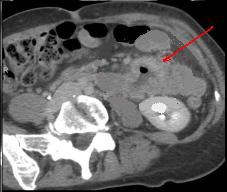

| Adeno carcinoma duodenum :

Epaissisement de la paroie duodenum en

circonferentielle , infiltrant et irreguliairement .

Image de stenose de la lumiere du portion lesionaire

. Image TDM en coupe axilae . |